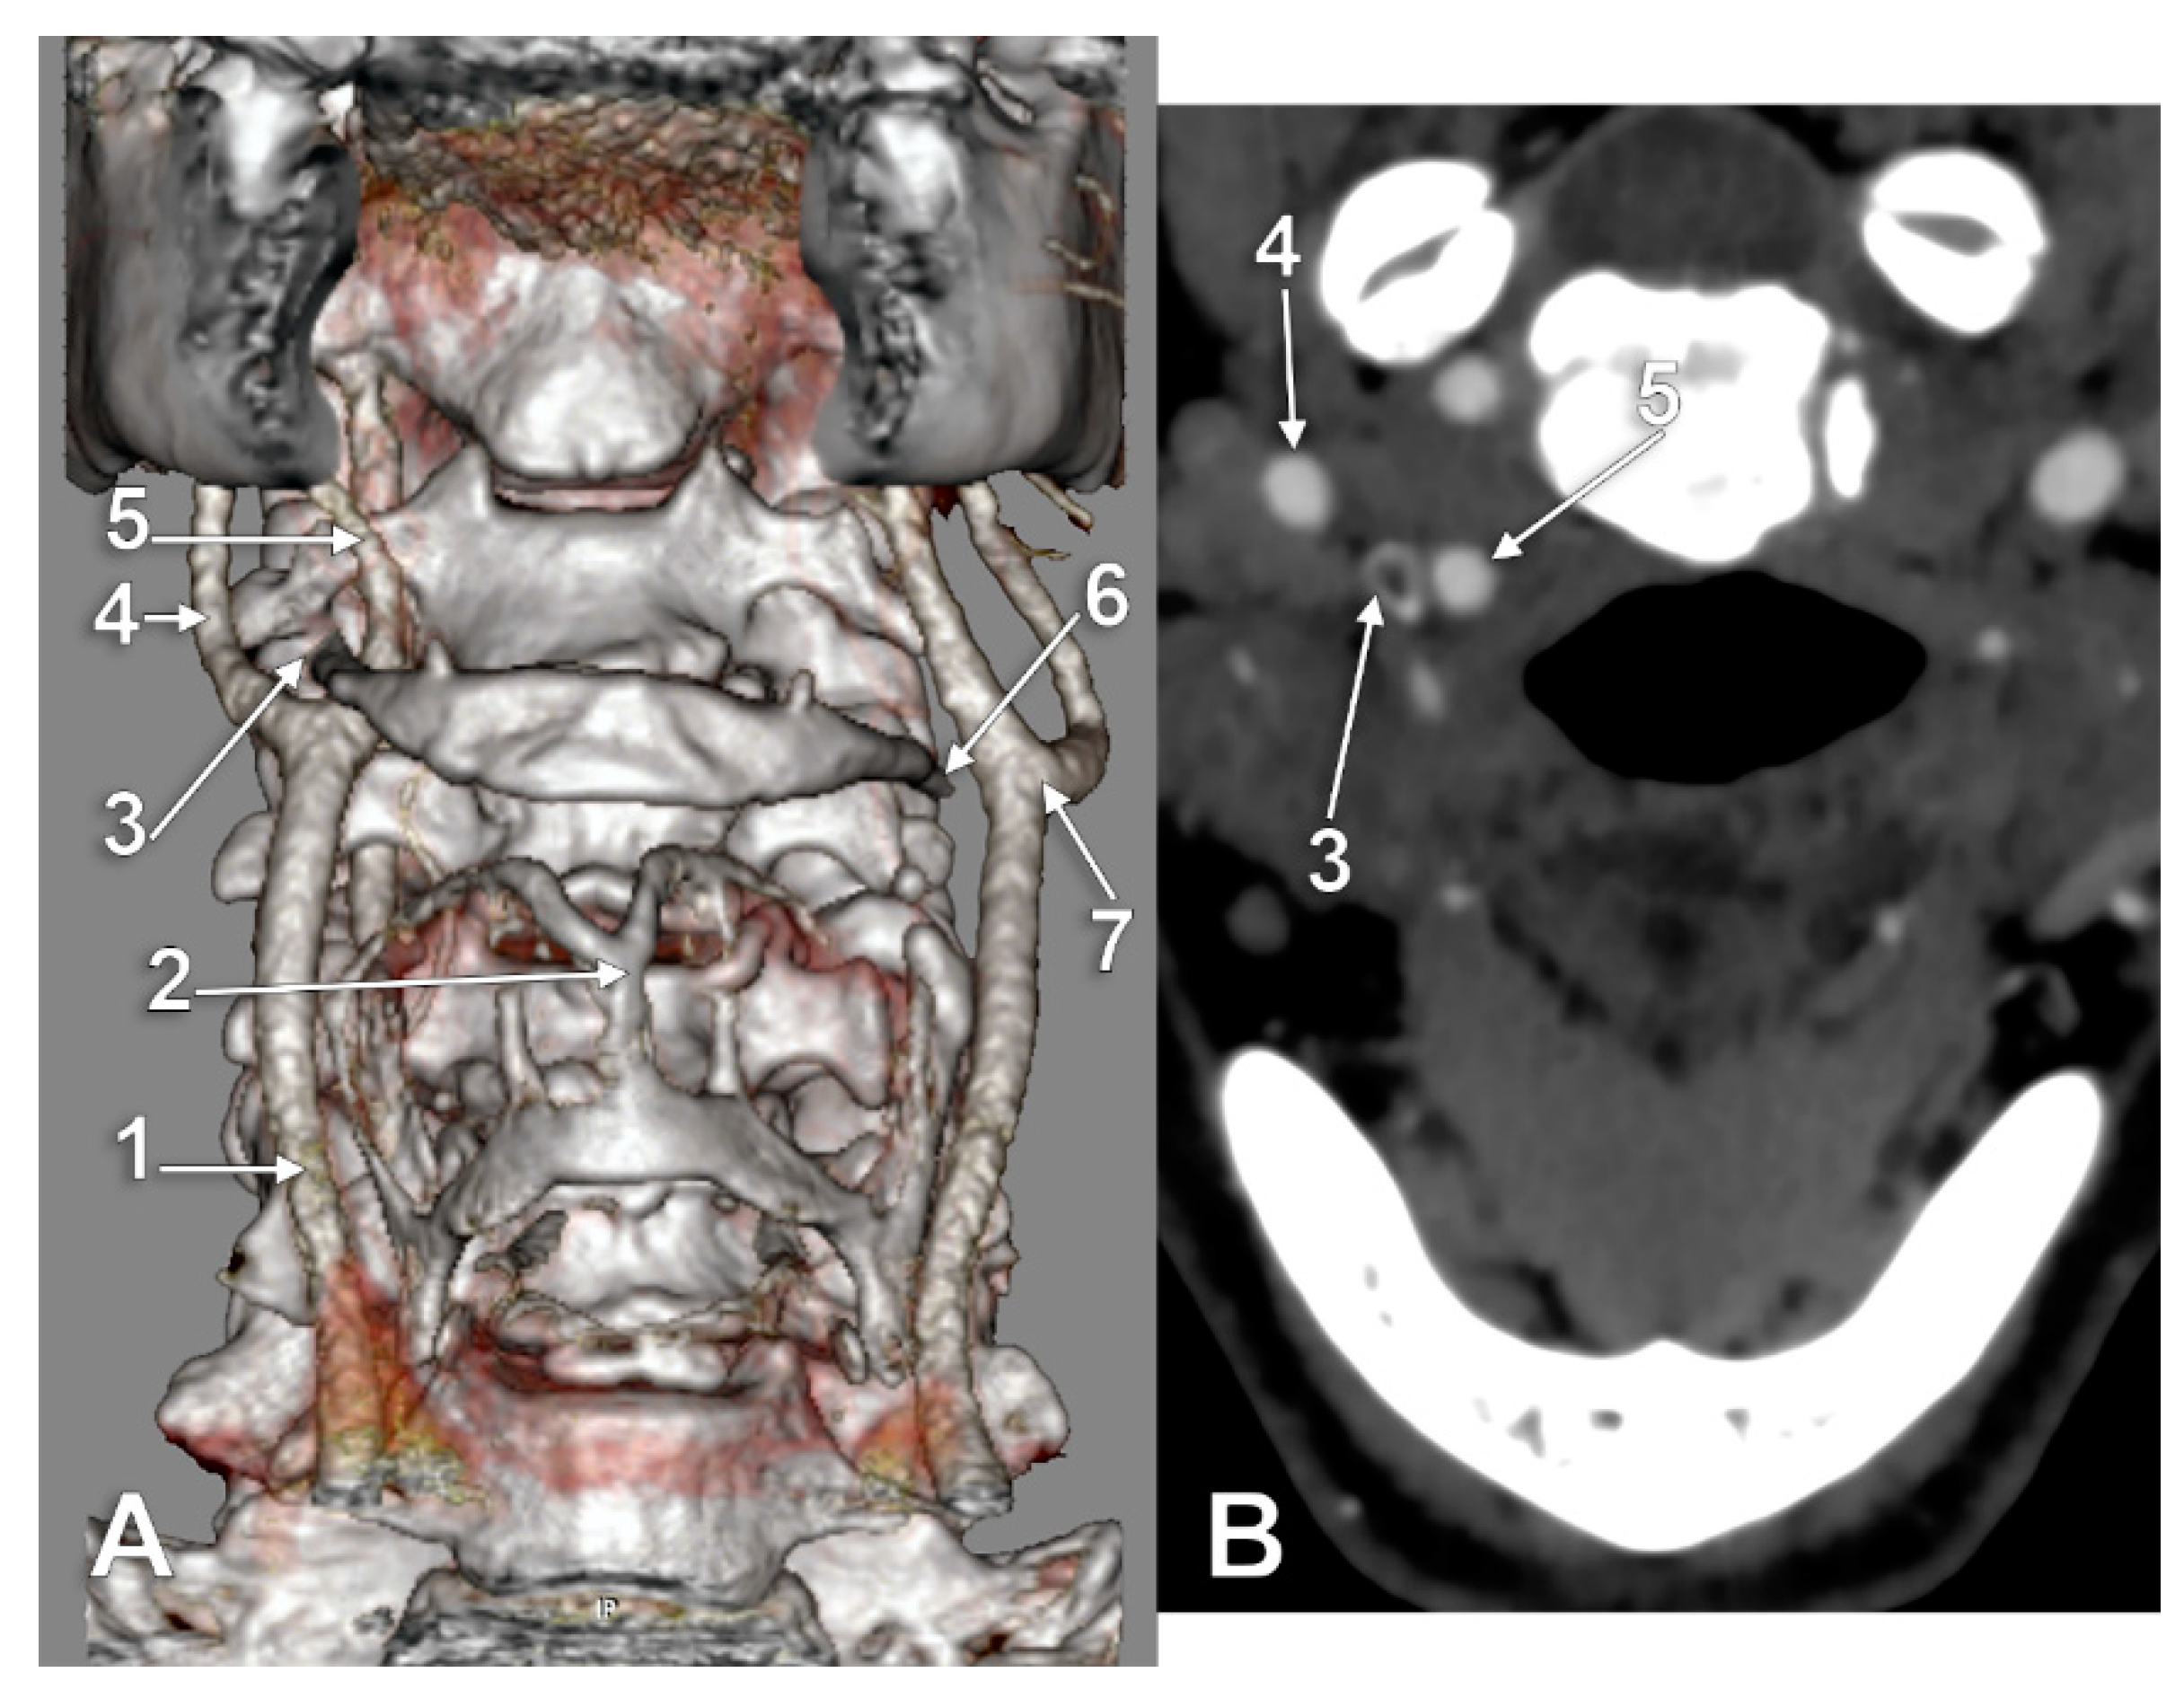

The Carotid–Hyoid Topography Is Variable

Manta, M.D.; Rusu, M.C.; Hostiuc, S.; Vrapciu, A.D.; Manta, B.A.; Jianu, A.M. The Carotid–Hyoid Topography Is Variable. Medicina 2023, 59, 1494. https://doi.org/10.3390/medicina59081494